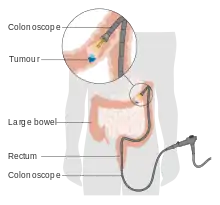

| Diagnostic method | Tissue biopsy during a sigmoidoscopy or colonoscopy[2] |

Bowel cancer may be diagnosed by obtaining a sample of the colon during a sigmoidoscopy or colonoscopy.[2] This is then followed by medical imaging to determine if the disease has spread.[2] Screening is effective for preventing and decreasing deaths from colorectal cancer.[1] Screening, by one of a number of methods, is recommended starting from the age of 45 to 75.[10] During colonoscopy, small polyps may be removed if found.[11] If a large polyp or tumor is found, a biopsy may be performed to check if it is cancerous. Aspirin and other non-steroidal anti-inflammatory drugs decrease the risk.[11][12] Their general use is not recommended for this purpose, however, due to side effects.[13]

Colorectal cancer diagnosis is performed by sampling of areas of the colon suspicious for possible tumor development, typically during colonoscopy or sigmoidoscopy, depending on the location of the lesion.[23] It is confirmed by microscopical examination of a tissue sample.

As more than 80% of colorectal cancers arise from adenomatous polyps, screening for this cancer is effective for both early detection and for prevention.[23][102] Diagnosis of cases of colorectal cancer through screening tends to occur 2–3 years before diagnosis of cases with symptoms.[23] Any polyps that are detected can be removed, usually by colonoscopy or sigmoidoscopy, and thus prevent them from turning into cancer. Screening has the potential to reduce colorectal cancer deaths by 60%.[103]

The three main screening tests are colonoscopy, fecal occult blood testing, and flexible sigmoidoscopy. Of the three, only sigmoidoscopy cannot screen the right side of the colon where 42% of cancers are found.[104] Flexible sigmoidoscopy, however, has the best evidence for decreasing the risk of death from any cause.[105]

Surgery

If the cancer is found at a very early stage, it may be removed during a colonoscopy using a variety of techniques including EMR and ESD.[2] For people with localized cancer, the preferred treatment is complete surgical removal with adequate margins, with the attempt of achieving a cure. The procedure of choice is a partial colectomy (or proctocolectomy for rectal lesions) where the affected part of the colon or rectum is removed along with parts of its mesocolon and blood supply to facilitate removal of draining lymph nodes. This can either be done by an open laparotomy or laparoscopically, depending on patient and lesion factors.[23] The colon may then be reconnected or a person may have a colostomy.[2]